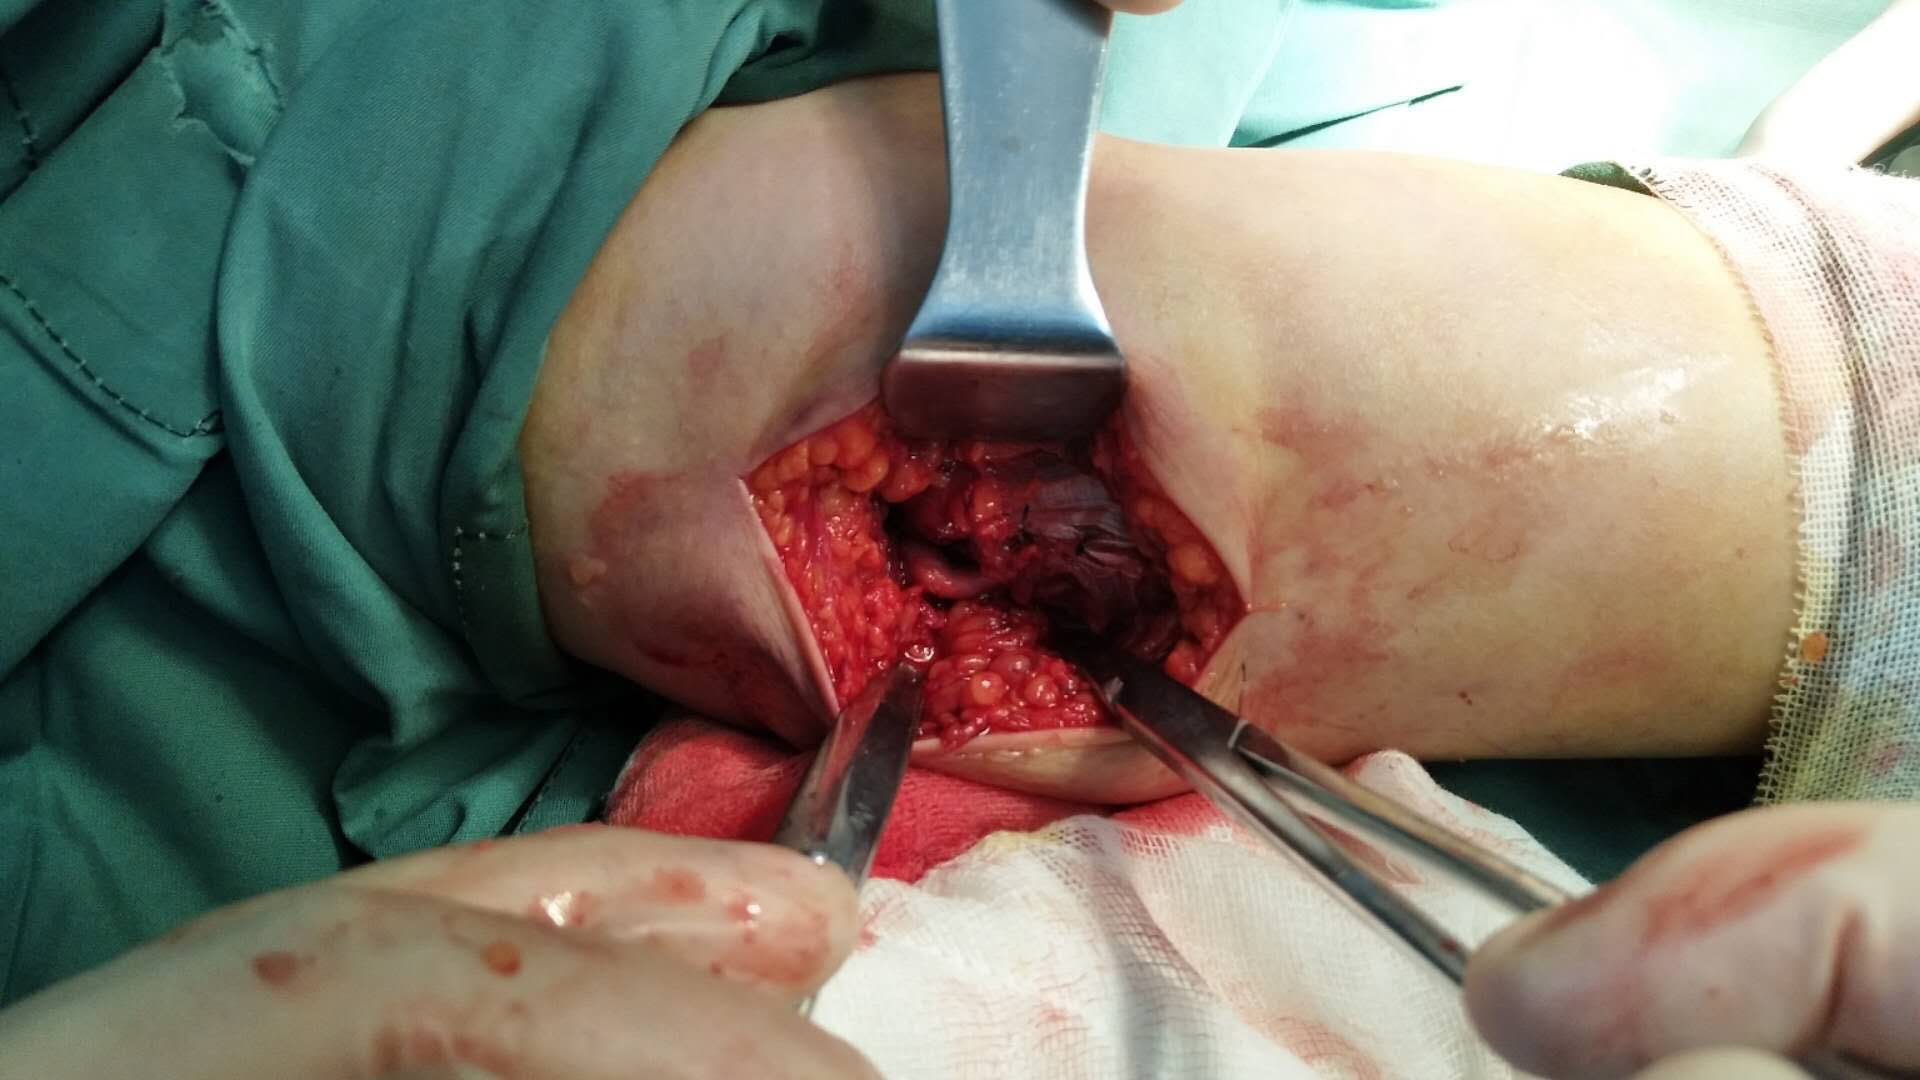

肱骨内髁屈肌腱总止点撕脱性骨折(止点重建,尺神经松解

摔伤后左肘部肿痛,活动受限1小时入院。既往身体健康,无特殊不良嗜好。

生命体征平稳,心肺复未见异常。左肘部肿胀明显,局部皮色发红,皮温高,压痛明显,肘关节侧搬试验内侧阳性,末梢血运正常,尺神经只配区稍感麻木。

诊断        左肱骨内髁屈肌腱总止点撕脱性骨折,   尺神经损伤在臂丛麻醉下行切复内固定,止点重建,尺神经松解术,术后石膏托固定,抗炎,消肿等处理。